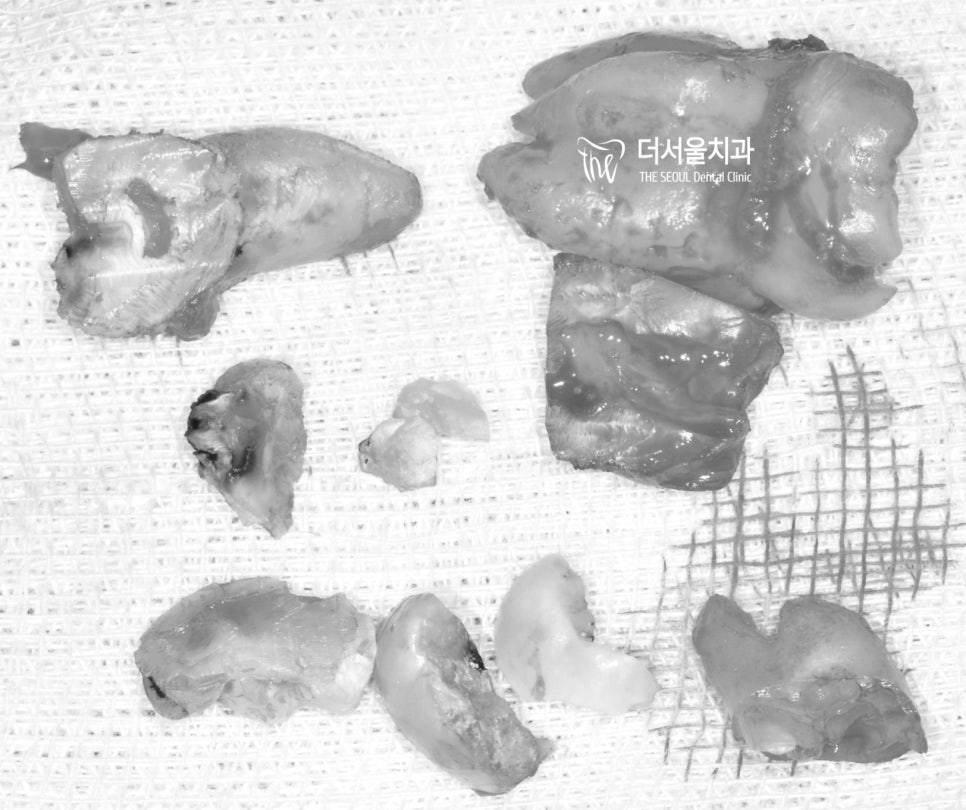

뭐… 결과는 잘 뽑아드렸습니다.

단, 우측 윗 사랑니는 뽑는데

난항이 있어서 조각조각 쪼개어

이를 뽑아줄 수밖에 없었죠.

큰 부작용없이 잘 뽑은게 다행이라 생각합니다.

물론 술자의 오랜 경력이 큰 도움이 되었겠죠.

수술이 잘 끝나고 환자분께 사랑니를 보여드리며

발치는 잘 끝마쳤다고 말씀드리니

“Wonderful!” 하며 엄지척을 해주셨습니다. ^^